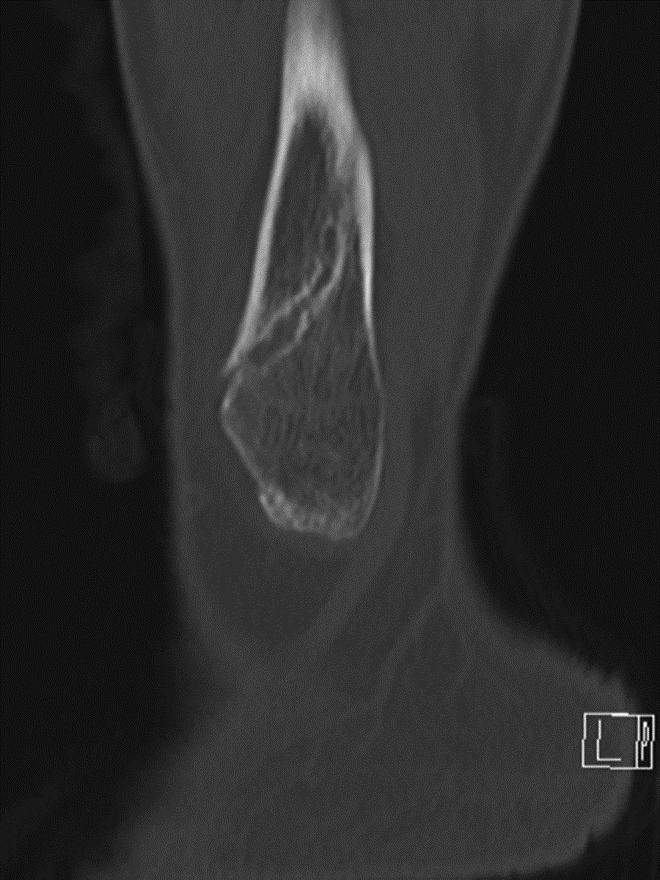

Just as with the immediate post-operative setting, CT is the modality of choice for evaluating complications related to spinal fusion. Screw fracture may occur in up to 25% of patients (Figure 13) (Ohashi, 2009; Lonstein, 1999). As with all cases of hardware failure, the imaging findings should be correlated with patient symptoms as not all hardware complications relate to current clinical symptoms. CT can be useful for the detection of polyethylene dislocation, which may occur in shoulder, hip and knee arthroplasties, and may be difficult to detect on radiographs (Figure 14) (Clarke, 2004).

Polyethylene Liner Displacement. Sagittal multiplanar reformation of reverse total shoulder arthroplasty demonstrates posteriorly displacement of low attenuation polyethylene liner relative to the humeral component and glenosphere in patient with limited range of motion.